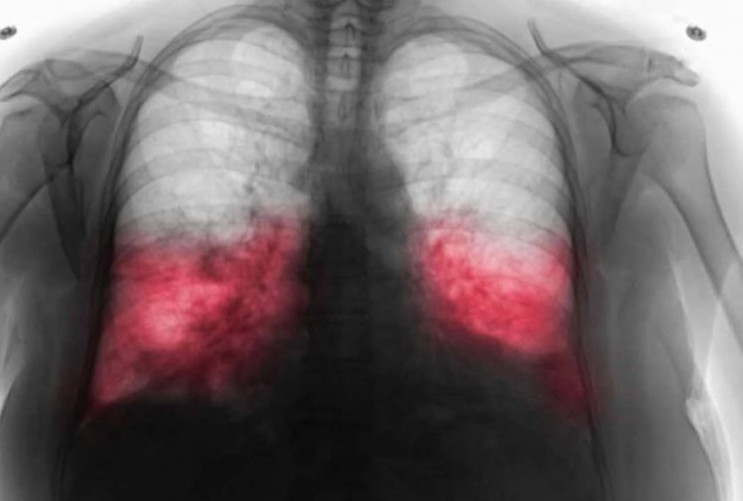

Dijagnoza hodajuće upale pluća zahtijeva detaljan medicinski pregled, koji može uključivati laboratorijske testove i rendgenske snimke pluća. U nekim slučajevima, ljekar može uzeti bris iz dišnih puteva da bi precizno odredio uzročnika infekcije. Liječenje obično uključuje specifične antibiotike koji su usmjereni protiv bakterija koje uzrokuju bolest. Važno je da pacijenti završe propisanu terapiju kako bi se izbjegli recidivi i dugotrajne posljedice. Na primjer, jedan od najčešće korištenih antibiotika za liječenje hodajuće upale pluća je azitromicin, koji se pokazao efikasnim protiv Mycoplasma pneumoniae. U nekim slučajevima, ukoliko pacijent ima alergiju na određene antibiotike, ljekar može preporučiti alternativne tretmane. Također, važno je napomenuti da se simptomi mogu pogoršati ukoliko se bolest ne liječi, što može dovesti do ozbiljnijih stanja poput pleurisa ili čak respiratornog zatajenja.